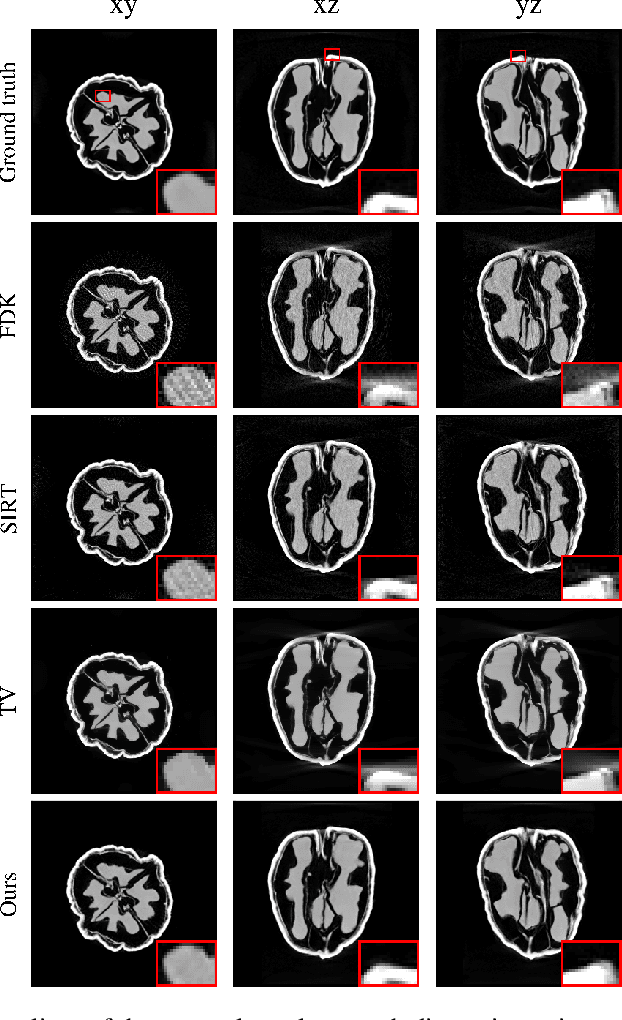

Abstract:Learned iterative reconstruction algorithms for inverse problems offer the flexibility to combine analytical knowledge about the problem with modules learned from data. This way, they achieve high reconstruction performance while ensuring consistency with the measured data. In computed tomography, extending such approaches from 2D fan-beam to 3D cone-beam data is challenging due to the prohibitively high GPU memory that would be needed to train such models. This paper proposes to use neural ordinary differential equations to solve the reconstruction problem in a residual formulation via numerical integration. For training, there is no need to backpropagate through several unrolled network blocks nor through the internals of the solver. Instead, the gradients are obtained very memory-efficiently in the neural ODE setting allowing for training on a single consumer graphics card. The method is able to reduce the root mean squared error by over 30% compared to the best performing classical iterative reconstruction algorithm and produces high quality cone-beam reconstructions even in a sparse view scenario.